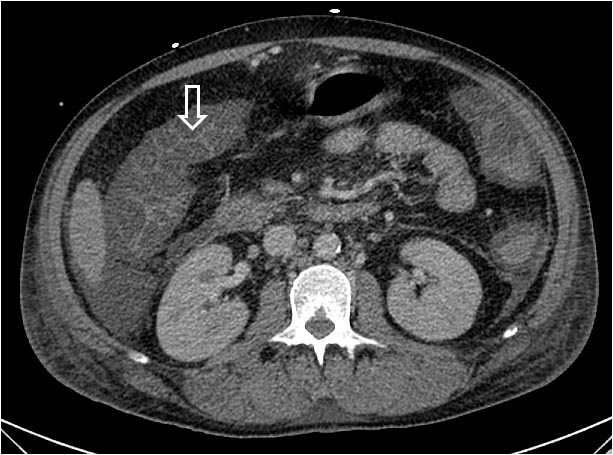

SIGNO DE LA CABEZA DE FLECHA o PUNTA DE FLECHA

Signo visible en la TC con contraste oral, que debe alcanzar hasta el ciego. El signo hace referencia al engrosamiento focal del ciego centrado en el orificio apendicular. El contraste rellena la luz del ciego y se dispone en forma de cabeza de flecha apuntando hacia el apéndice. Es un signo indirecto de apendicitis.

Su valor es escaso. En primer lugar porque en la mayoría de los casos, el diagnóstico de apendicitis puede hacerse con ecografía o con TC sin contraste oral.